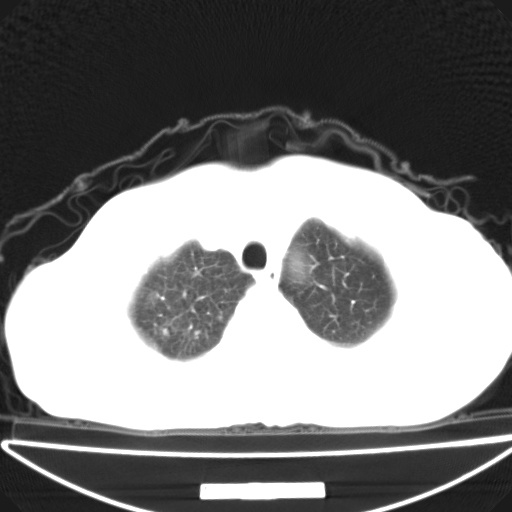

以下是引用jsgdoctor在2008-11-6 22:12:00的发言:[br]右主支气管壁明显增厚,管腔狭窄.考虑为右侧中央型肺癌伴阻塞性炎症\\肺脓肿.

以下是引用zjzjr在2008-11-6 20:25:00的发言:[br]中心型肺ca,合并阻塞性肺炎

以下是引用zsl6918在2008-11-6 19:43:00的发言:[br]右侧中心性肺癌(鳞癌)